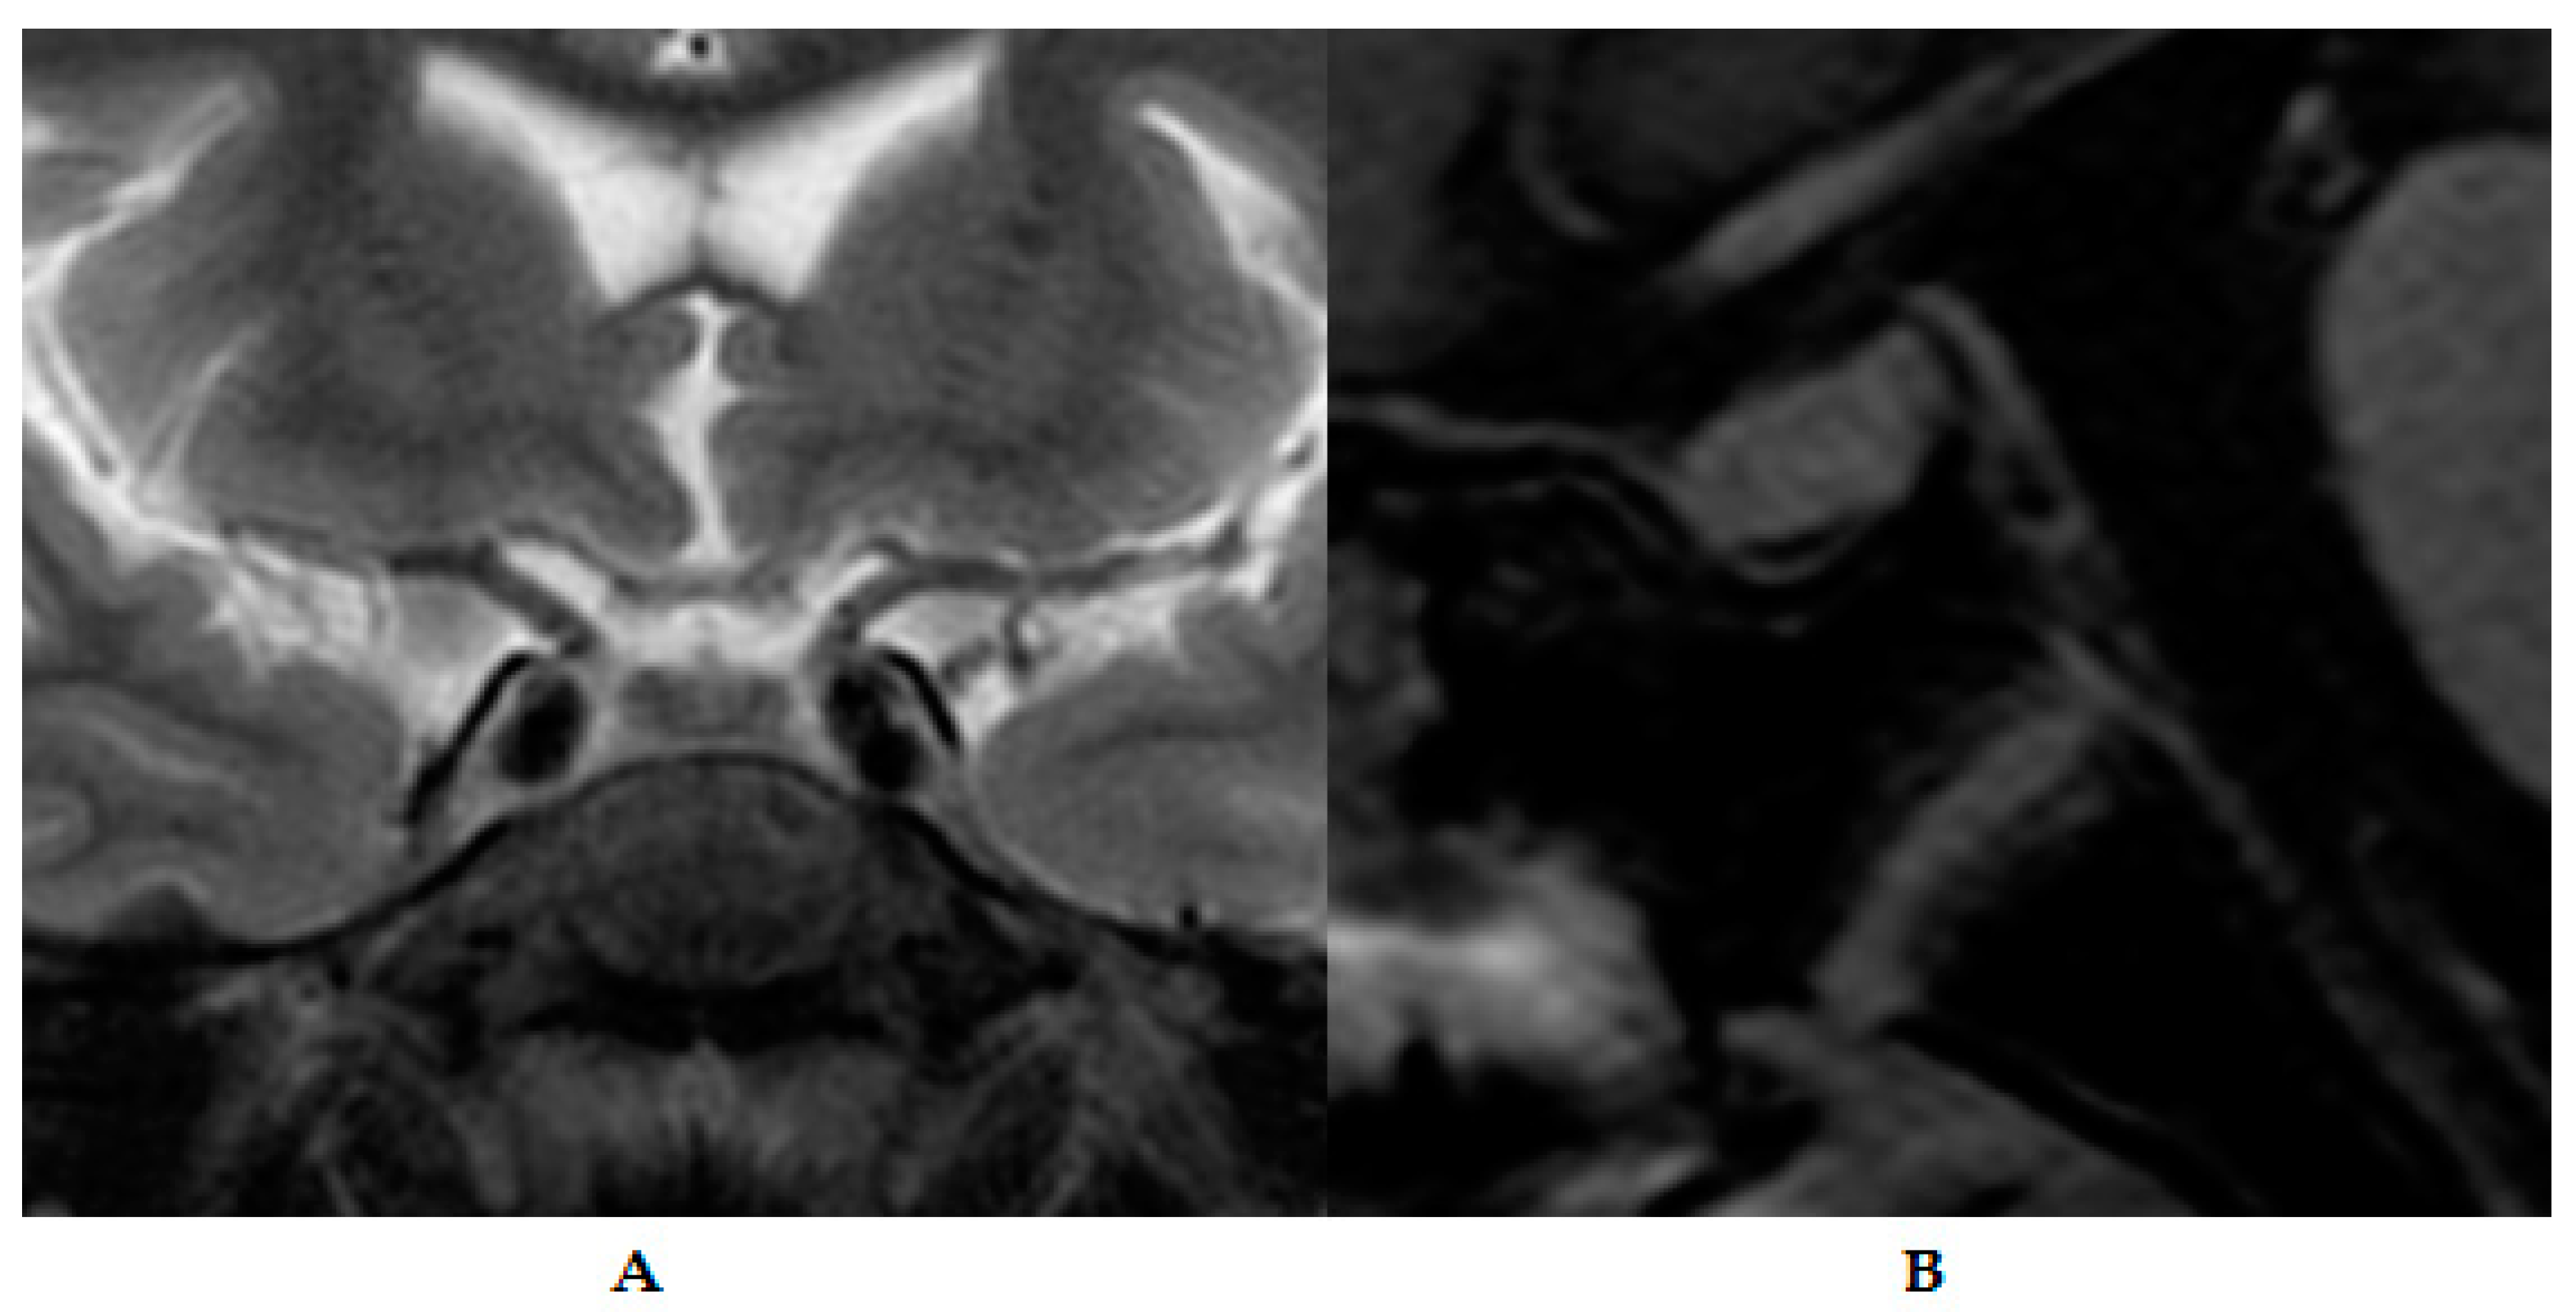

2. Detailed Case Description